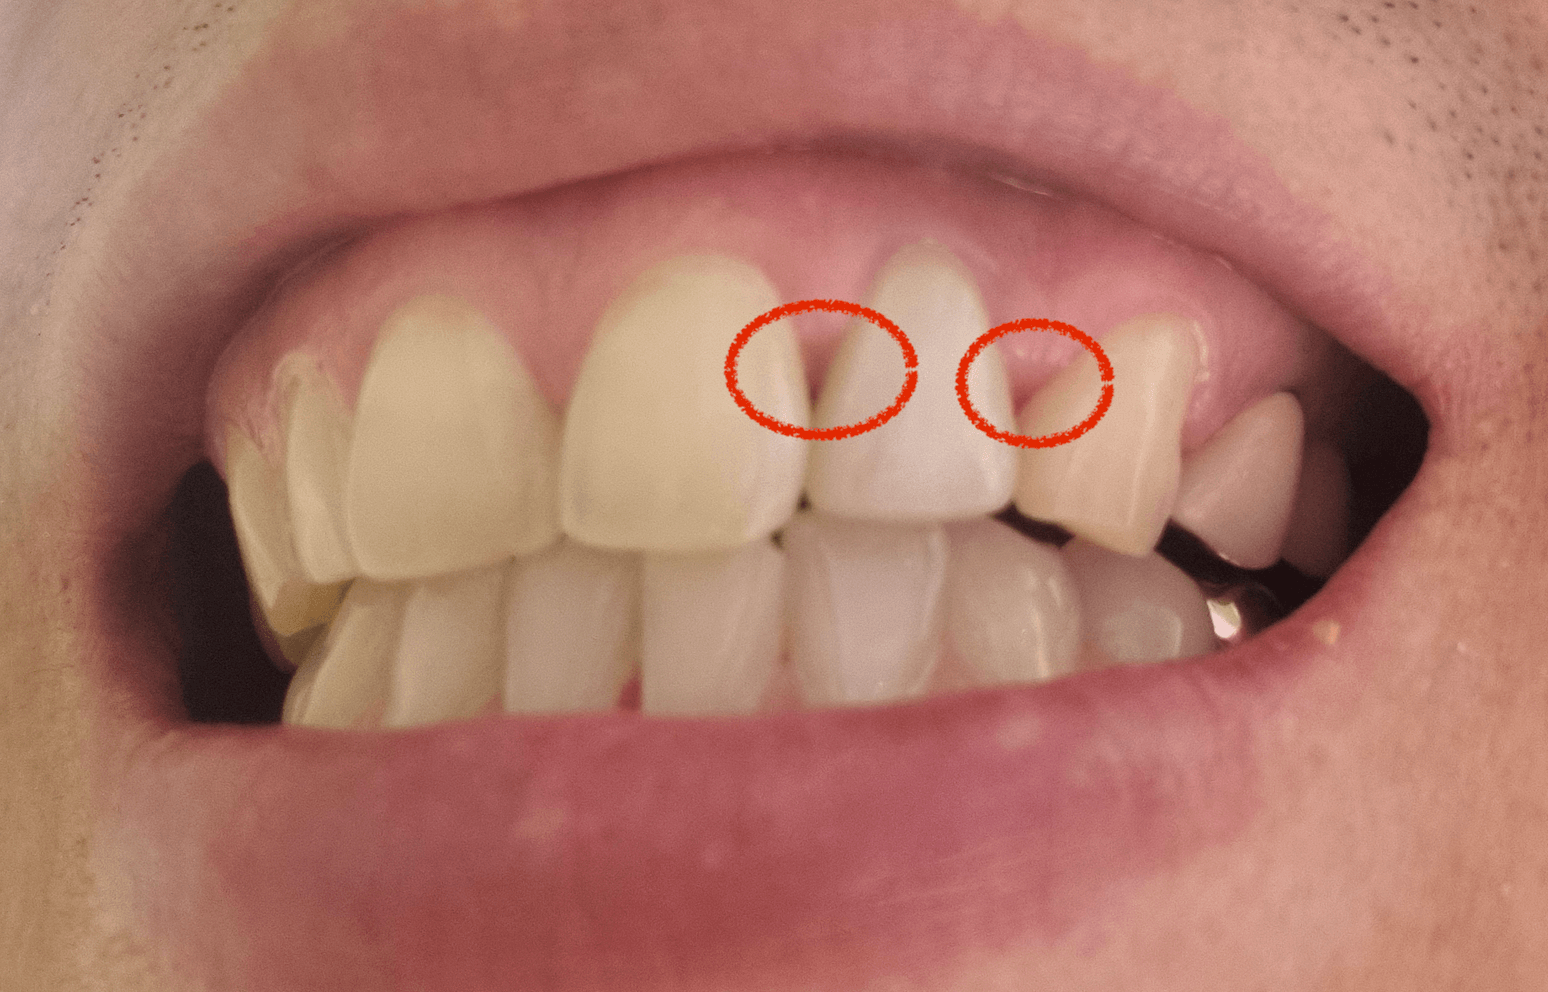

치근단절제술을 진행한 사람으로써, 생각보다 통증이 있으며, 수술후 글쓴이는 약간의 부작용이 생겨 아직도 잇몸이 치아사이로 끝까지 내려오지 않아 치아와 치아사이 잇몸이 비어있는 어색한 사항을 만들어 내고 있습니다.

개인적으로 이럴줄 알았으면, 차라리 그냥 임플란트를 하는것이 더 좋았지 않았나 합니다. 선택은 본인의 몫이고, 저처럼 치아는 살렸지만, 수술후 잇몸이 치아사이를 덮어주지 않아 치아가 벌어진것처럼 약간의 구멍이 났습니다. 아래 치근단절제술을 알아보면서 개인적 이야기도 더해 보겠습니다.

치근단절제술은 우리의 치아를 살릴수 있는 마지막 보류라고 생각해도 됩니다. 다만, 저같은경우 수술후 잇몸이 치아와 치아사이 끝까지 내려오지 않아 치과 의사에게 물어 봤더니, 나이가 들면 잇몸이 끝까지 내려오지 않을수도 있다는 황당한 말을 들었습니다.

그런데 이런 사항이 저뿐만 아니라 찾아보니 그런분들도 꽤있었습니다. 이럴줄 알았으면 그냥 잇몸을 절개하지 않고 앞니를 뽑고 임플란트를 하는게 더 나을뻔 했습니다.

웃을때 보면 치아와 치아사이 잇몸이 끝까지 내려오지 않고 약간의 구멍이 나있어 거기에 음식물끼어 상당히 불편하네요. 만약 치근단절제술을 받을려고 하신다면, 이러한 점을 생각하시에 꼭 치과의사선생님께 이런 사람이 있더라 그러니 잇못이 치아까지 내려올수 있도록 잘해 주세요말을 꼭 한번은 해주세요.

그래야 조금이라도 더 신경을써서 해주지 않을까 합니다. 개인적으로 저는 이게 상당히 불만이고 웃을때마다 신경이 쓰이는 흠이 되었네요, 나는 치료만 받았을 뿐인데 말입니다. 이상으로 치근단절제술 후기 보험 비용 통증 포스팅을 줄입니다.